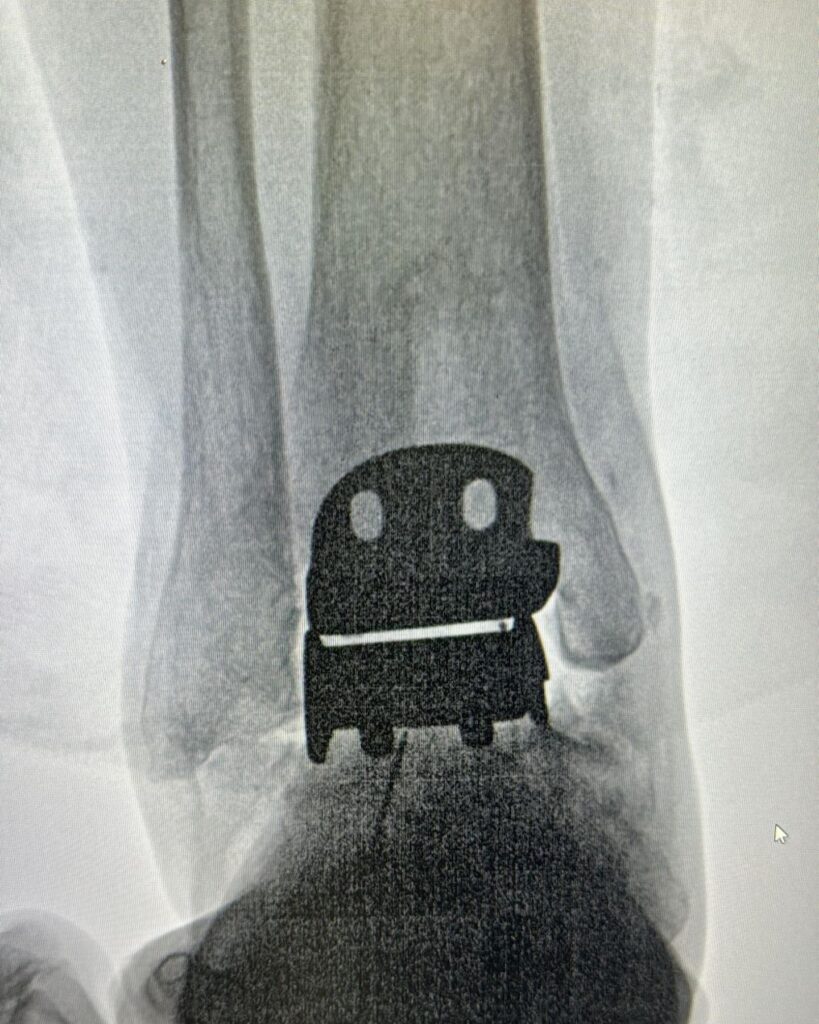

Este procedimiento quirúrgico consiste en sustituir la articulación dañada por una prótesis compuesta de metal y plástico, diseñada para restaurar la movilidad y aliviar el dolor.